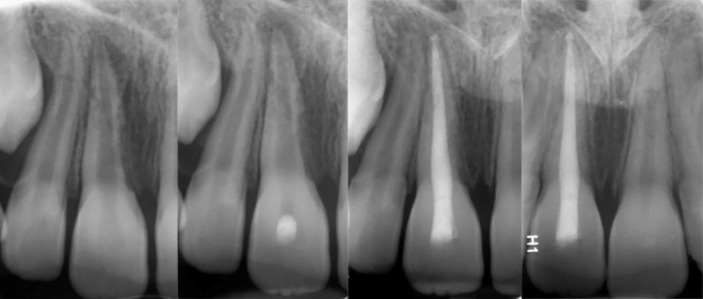

Bio-obturation is an innovative approach in root canal therapy that effectively addresses complex clinical challenges using bioactive endodontic materials. This report highlights 14 diverse cases where bio-obturation was employed to manage complications such as internal and external resorption, root perforations, draining sinus tracts, mechanical obstructions, and trauma-related injuries. The outcomes demonstrate notable healing and resolution of various tooth related pathologies in failed primary root canal treatments. Root perforations and canal blockages were successfully sealed, restoring the integrity of the root canal system and ensuring continued tooth function and retention. Bio-obturation facilitated stabilization and regeneration of periradicular and supporting tissues in trauma cases, including avulsed teeth and inflammatory root resorption. Cases involving open apices, dens invaginatus, and complex root canal anatomy also showed favorable results. Overall, bio-obturation offers a transformative alternative to conventional root canal filling by promoting enhanced biological sealing and improved periradicular healing, thus increasing the probability of sustainable long-term clinical success. While calcium-enriched mixture cement served as the bioactive material in these cases, this approach may also be effectively implemented using other advanced calcium silicate-based biomaterials, broadening its applicability in challenging endodontic scenarios.